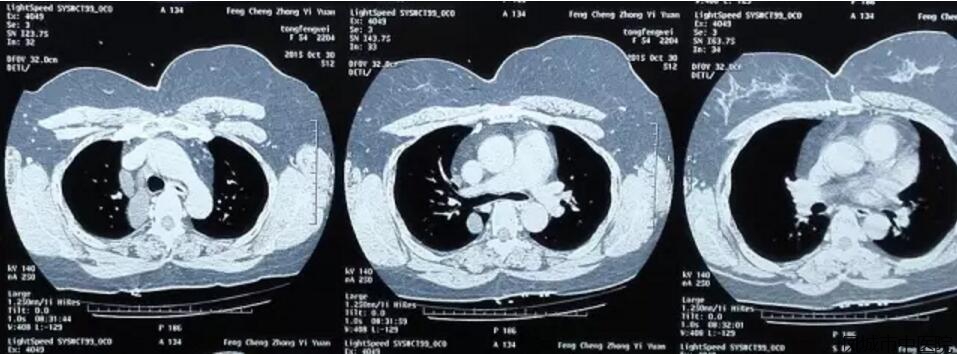

我院外一科在全麻下成功开展一例开胸直视下右侧心包囊肿切除术,为我院第一例该项手术。

该患者自觉胸闷不适多年,近期有刺激性干咳,术前检查发现右侧胸腔囊性肿物约5X4X3cm大小。

经过科内充分术前准备,成功顺利完成手术,患者术后恢复良好。